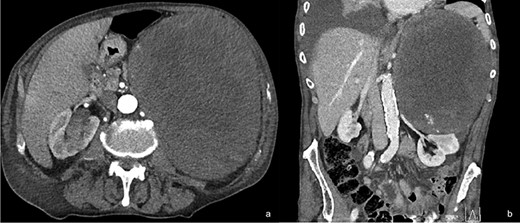

The patient reported a previous history of left non-secreting adrenal incidentaloma, diagnosed 10 years before. At the time of diagnosis, the tumor diameter was 2.3 cm, with CT densitometry suggestive for benign adenoma (Fig. 2); the patient had been invited to regular follow-up visits, which he never attended. After 6 years, a new contrast CT demonstrated a growth of the tumor up to 7 cm. The clinical examination had excluded symptoms and signs of adrenal hormonal excess. A new complete evaluation of the endocrine situation was repeated: 1 mg overnight dexamethasone suppression test excluded cortisol excess; pheochromocytoma was excluded by the measurement of urinary fractionated metanephrines; because the patient was hypertensive, aldosterone/renin ratio was performed after 2-month washout from interferent antihypertensive drugs and a primary aldosteronism was excluded; all other laboratory tests were regular. The patient was asymptomatic and decided to discontinue his follow-up, coming back to medical attention the day of the trauma. After treatment of the hemothorax, the patient recovered completely and was discharged. Subsequently, he was submitted to abdominal open surgery through an anterior approach. A Chevron bilateral subcostal incision was made; the left colon mobilized, with careful dissection of the mesocolon from the mass. The left retroperitoneal space was accessed, displaying an imposing vascularized mass occupying the upper left abdomen (Fig. 3a–d). The mass displaced the left kidney, determining a verticalization downward of the left renal artery and vein and was in close contact with the upper pole of the kidney without having clear cleavage plans (Fig. 1b). On the other hand, the splenic artery and vein were displaced vertically upward. Careful dissection of the mass allowed its complete removal without damaging the surrounding organs and vessels, with ligation of the adrenal vein (Fig. 3d), as well as large lumbar vessels vascularizing the mass. Blood loss was 2500 cc, and the patient was transfused with 5 units of concentrated red blood cells. Final dimensions of the mass on the operating table were 26 × 21 × 12 cm, weight = 4.5 kg (Fig. 4). Two abdominal drains were left in place and removed on the fourth and fifth postoperative day. The postoperative clinical course was uneventful, and the patient was discharged on the seventh postoperative day without complications. At 6-month follow-up visit, the patient presented no symptoms and no signs of recurrence.

Ten years before abdominal CT scan, provided by the patient, at the time of first diagnosis, showing a 2.3-cm mass at the level of the left adrenal gland (green circle).